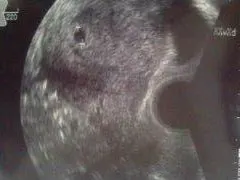

そして、産婦人科を受診して来ました。モモちゃんの時には初回受診で胎のうが確認出来ずハラハラしましたが、今回はちゃんと見えました♪

GS7.1mm。

ちゃんと子宮内に着床していました。